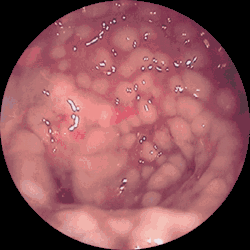

![]() Endoskopowy obraz rzekomobłoniastego zapalenia jelit | |

Rzekomobłoniaste zapalenie jelit (RzZJ, łac. enterocolitis pseudomembranacea, ang. pseudomembranous enterocolitis) – ostra choroba biegunkowa jelita cienkiego lub grubego. Charakterystyczna dla niej jest obecność szarożółtych błon rzekomych na powierzchni błony śluzowej.